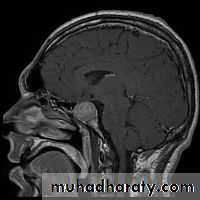

MRI scan of the pituitary region